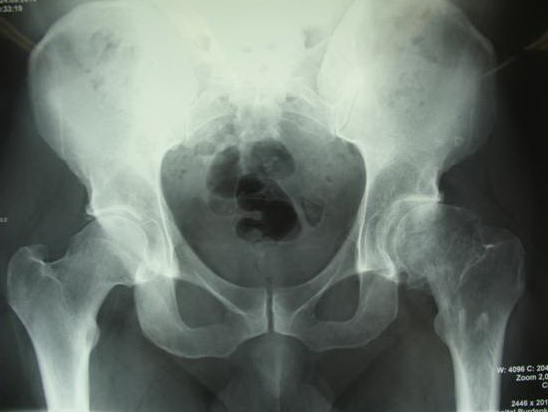

На сегодняшний день общепризнано, что эндопротезирование тазобедренного и коленного суставов является единственным эффективным методом лечения при разрушении суставного хряща и позволяет избавит пациента от боли и вернуть его к активной жизни. В мире ежегодно выполняется более полутора миллионов таких операций. Современные эндопротезы служат десятки лет и позволяют жить полноценной жизнью даже молодым и активным пациентам, а в случае, если эндопротез всё же износился, его можно заменить на более сложный и продолжать пользоваться всеми благами жизни.

Ортопедическое отделение Главного военного клинического госпиталя им. акад. Н.Н.Бурденко занимается вопросами эндопротезирования крупных суставов более 30 лет. Мы прошли весь тернистый путь проб и ошибок в освоении этой специальности, познали горечь неудач и радость успеха. В отделении разработаны и запатентованы: уникальная методика двухэтапного эндопротезирования тазобедренных суставов, новые способы костнопластического замещения значительных дефектов вертлужной впадины при ревизионных операциях.

В последние годы мы активно занимаемся проблемой эндопротезирования тазобедренного сустава у молодых пациентов, в том числе при врождённой патологии (дисплазии) используя при этом новейшие высококачественные долговечные эндопротезы.